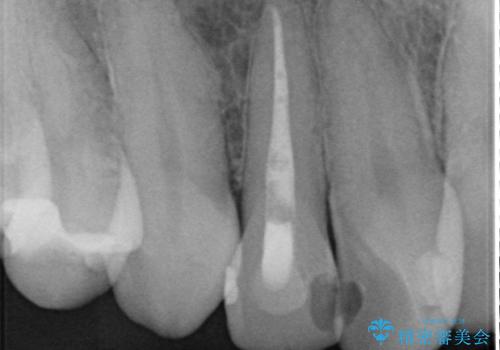

- 右上2番目の歯の変色が気になるといらっしゃった方の症例です。

再根管治療終了後、オールセラミッククラウンによる補綴を行いました。

今回用いたオールセラミッククラウンはジルコニアフレームという白い素材の上にセラミックを盛っているため、審美性が非常に高いのが特徴です。

また、ジルコニアは人工ダイヤモンドの材料にも使われているほど高い強度を持っており、そのためオールセラミッククラウンは審美性だけでなく、奥歯やブリッジの補綴も可能とするクラウンです。